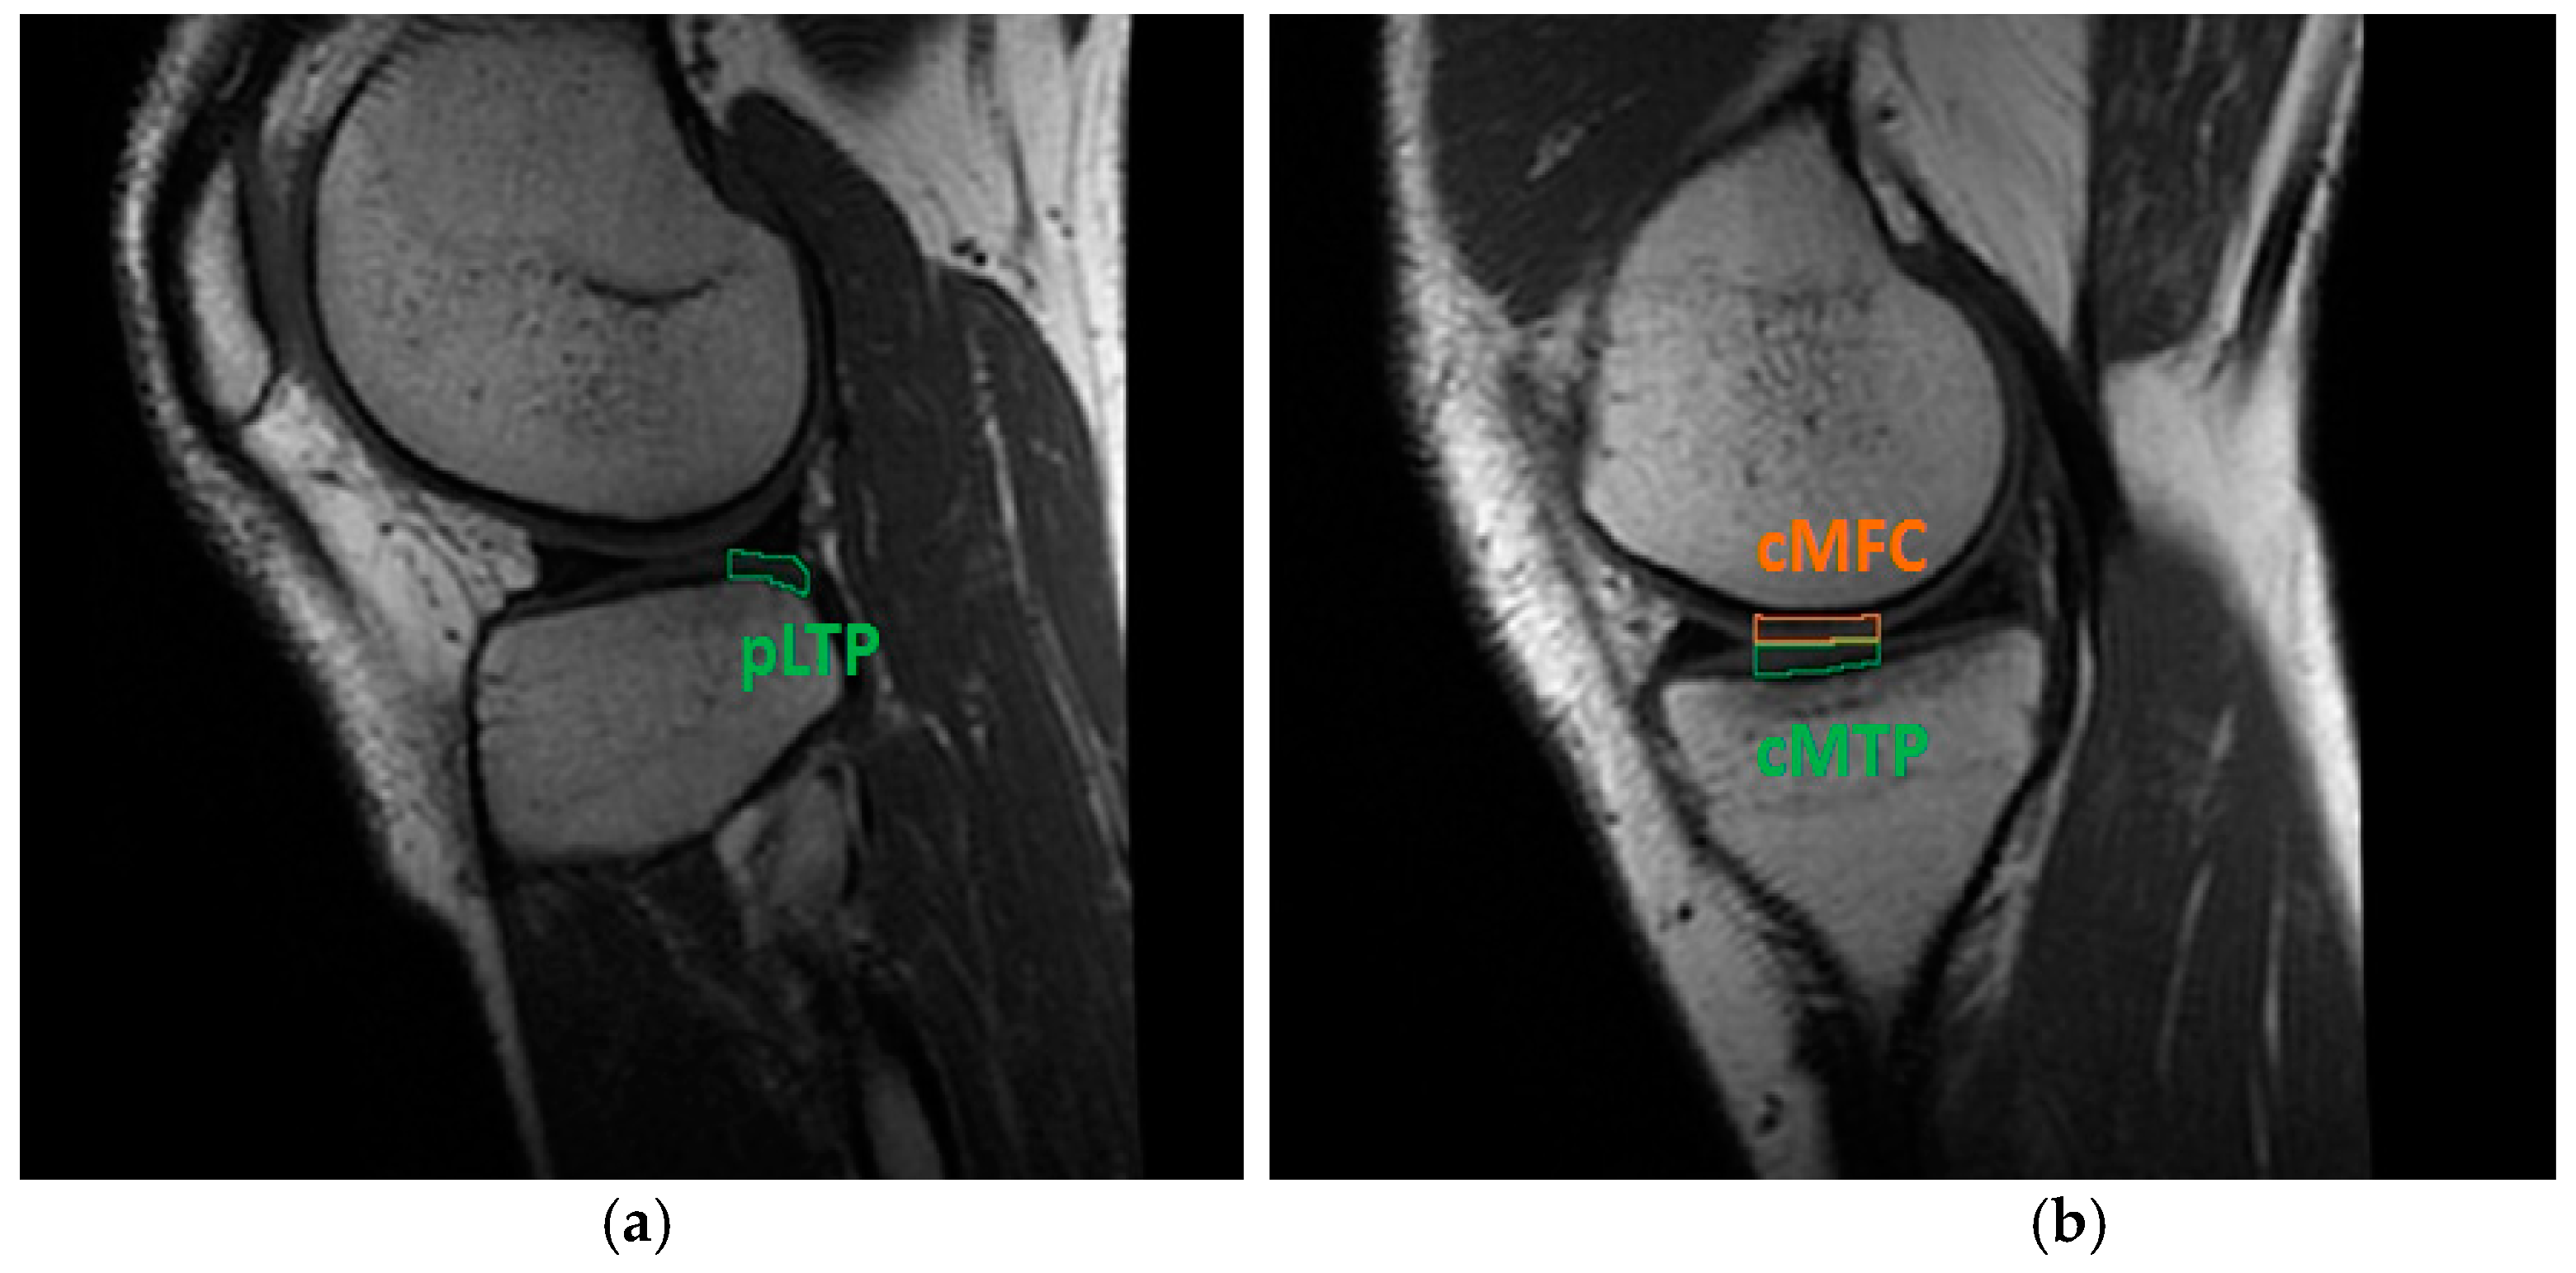

Concerning the assessment of the knee cartilage status via T2 signal, and according to relevant scientific literature, the regions of interest (ROIs) able to significantly highlight any onset of early cartilage degeneration are the posterior lateral tibial plateau (pLTP), the central medial tibial plateau (cMTP), and the central medial femoral condyle (cMFC) (Figure 2) [6,38]. Each sequence was therefore divided on a slice-by-slice basis and by anatomical markers, specifically by the menisci of the knee [39]. The mid-sagittal slice was selected for the evaluation of the T2 signal in the above-mentioned ROIs [36], specifically by following the same procedure previously reported for the assessment of ligaments and graft.

Cartilage ROIs evaluated through T2 mapping software: (a) pLTP portion in the lateral knee compartment; (b) cMFC and cMTP regions in the medial compartment. Data concern subject #6 at four months follow-up.